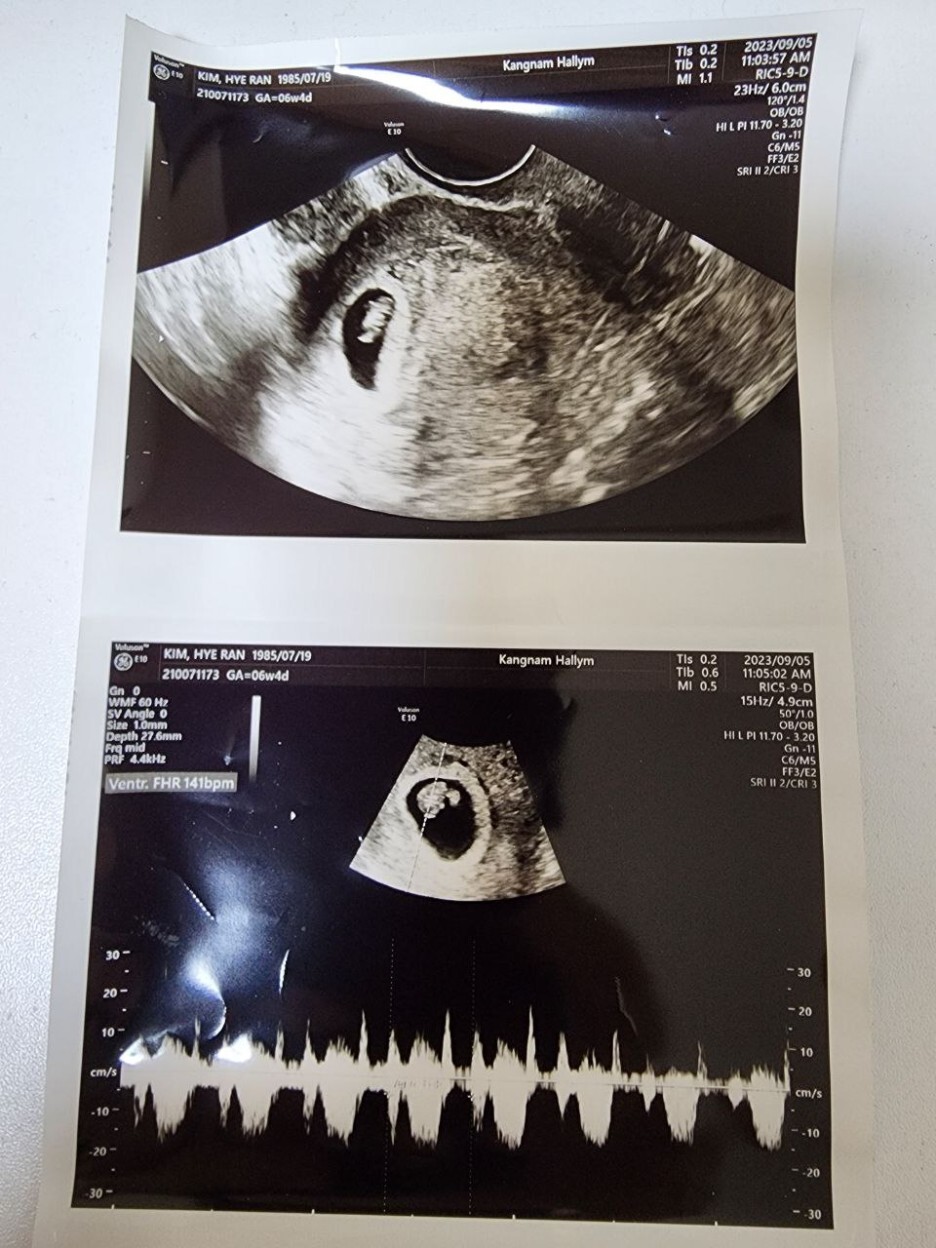

원래 초기에는 항상 그렇듯 병원을 자주 방문하게 된다. 보통 안정기에 접어드는 20주차 안에 유산되는 경우가 종종 있기 때문이다. 어차피 이 기간 안에 유산이 되는 경우는 내가 어찌할 수 없는 경우가 대부분이다. 게다가 태동을 전혀 느낄 수 없기 때문에 아기가 잘 있는지 아닌지 알기도 어려워 오로지 산부인과에 방문해서 초음파를 보는 방법 밖에는 불안한 마음을 달랠 길이 없다. 그런 이유에서 임신 초기에 산부인과를 자주 방문하게 된다. 의사 선생님도 그런 내 마음을 아시는지 또 오라고 하셔서 거의 5일 만에 다시 병원을 방문했다. 의사 선생님 말로는 아기집 크기도 좋고 위치도 좋다고 걱정할 부분이 전혀 없다고 하셨다.